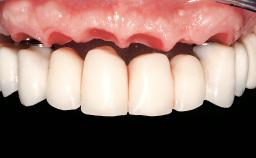

Immediate Loading of Six Implants in the Maxilla and Final Restoration with a Full-Arch Gold/Ceramic FDP Involving the Concept of Tilted Implants

A 61-year-old male patient with a failing fixed maxillary rehabilitation and a fixed mandibular rehabilitation requested a new fixed maxillary rehabilitation. The patient was wearing a temporary metal-reinforced maxillary bridge inserted two years before the consultation. He reported that his previous dentist did not want to insert a definitive framework because he considered the residual teeth to have a negative prognosis. The patient reported a history of recurrent caries and endodontic complications as the main reason for the previous extractions. The anamnesis was negative for periodontal disease and bruxism. The patient’s chief compliant was the mobility of his maxillary prosthesis, which needed to be re-cemented frequently, and discomfort during chewing.Moreover, the patient was not satisfied with the esthetic appearance of his maxillary teeth, which he found too long. The patient asked for a stable and comfortable fixed maxillary rehabilitation and firmly rejected any removable solution.

# of Implants 6

Prosthesis Type FDP